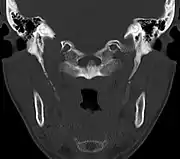

La apófisis alargada o calcificación del ligamento estilohioideo suelen mostrarse fácilmente a través de una prueba radiográfica. De forma adicional se puede realizar un TAC para confirmar el diagnóstico y ver qué estructuras están siendo afectadas.[10]